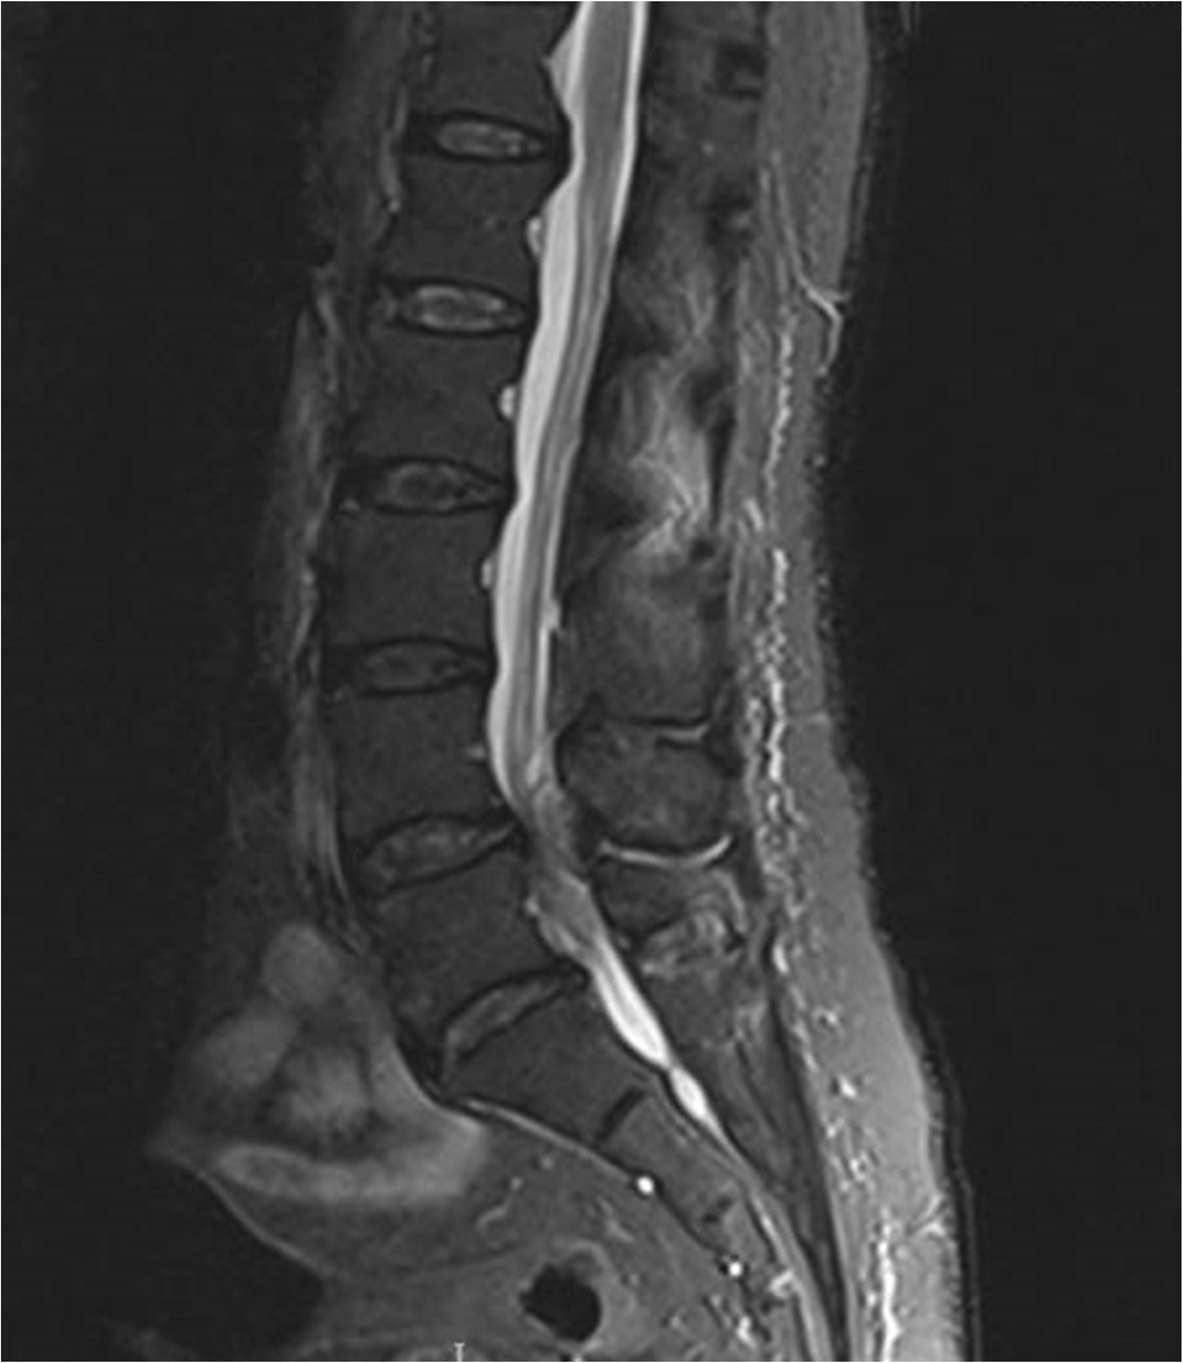

• MRI Whole Spine: This is the mainstay of diagnosis.

MRI demonstrating Cauda Equina syndrome